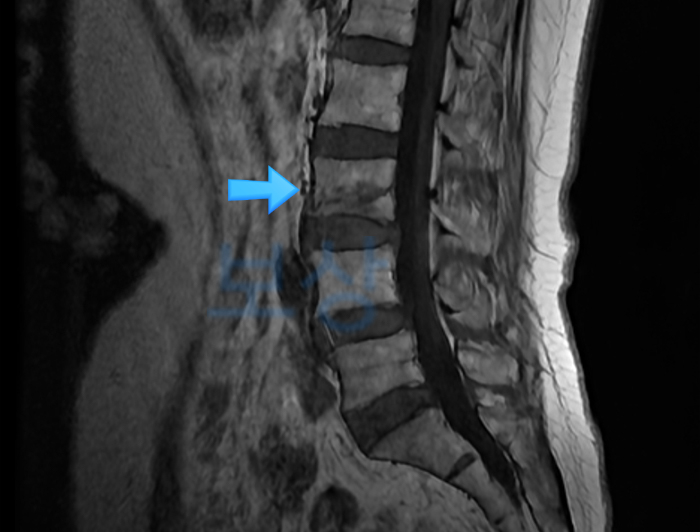

L2 부위의 골절, 폐쇄성 (S32030) ☞ 요추 2번 압박골절

경피적 척추체 성형술 경피적 경막외강 신경 유착박리술

제2요추 압박률 27%, 제12흉추 - 제3요추간 후만각 15도 측정됨. 보험약관상 장해지급률 30%(4급)에 해당함. 환자분의 경우에는 가입 금액 자체가 많지 않으셨기에 보상 금액이 그렇게 크지는 않으셨는데요.